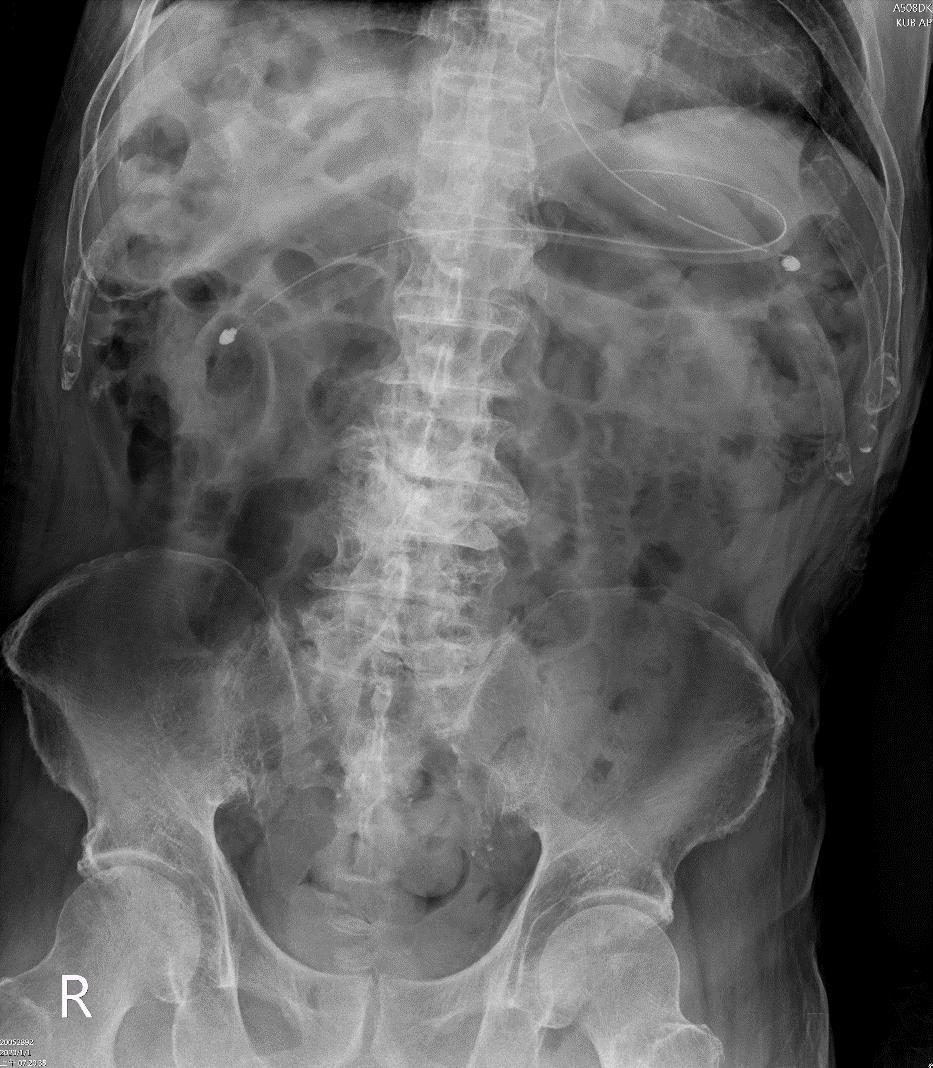

Figure 1: The KUB shows: Status post NG tube insertion, with another broken NG tube retained in stomach to duodenum.

A76 year old male with history of old CVAwith bed ridden, dementia, parkinsonism was sent to ER due to coffee ground noted from NG. Besides, right foot woud with swelling and mild fever was noted for one day, he was brought to a local clinicl where augmentin was prescribed. Initial laboratory exam showed only mild hyponatremia Na[126.0 mmol/L] and findings compatible with UTI.

According to his family, he was used to grinding teeth for a long time. An oral ulcer over left soft palate has been noted recently. A broken part of NG was noted 40 days ago when changing NG by a home care nurse, but no intervention was made with only observation to see if the broken NG can be passed out along with stool.